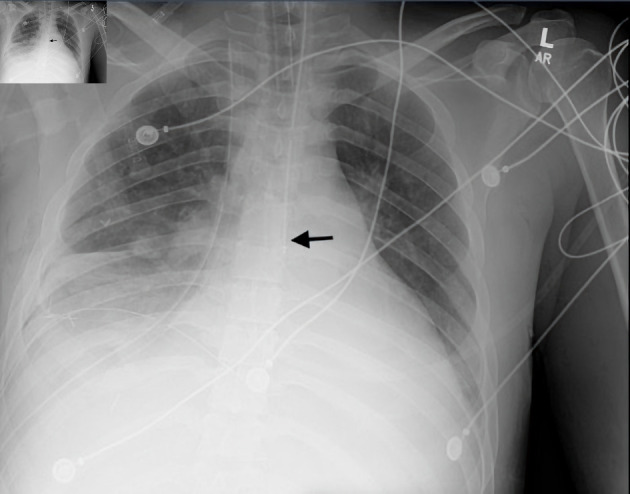

Orogastric tubes (OGTs) are frequently used to administer feeds and medications to critically ill patients. They are inserted blindly, with a low first-pass success rate and frequent benign complications. OGT fractures and ingestion are exceedingly rare, with only two cases reported to date. Herein, we describe a rare case of OGT transection and ingestion in a male patient admitted for hyperacute delirium and complicated pneumonia. The OGT remnant was retrieved using an endoscope without any complications. Clinicians must be aware of this rare but potentially catastrophic complication of OGT use. OGTs must be inspected in the same manner as endotracheal tubes to ensure patient safety.